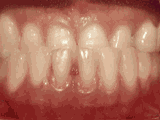

前牙移位,因为有牙齿缺失,导致相邻牙齿开始没有秩序的乱移动,经过矫正后是变成这样的~